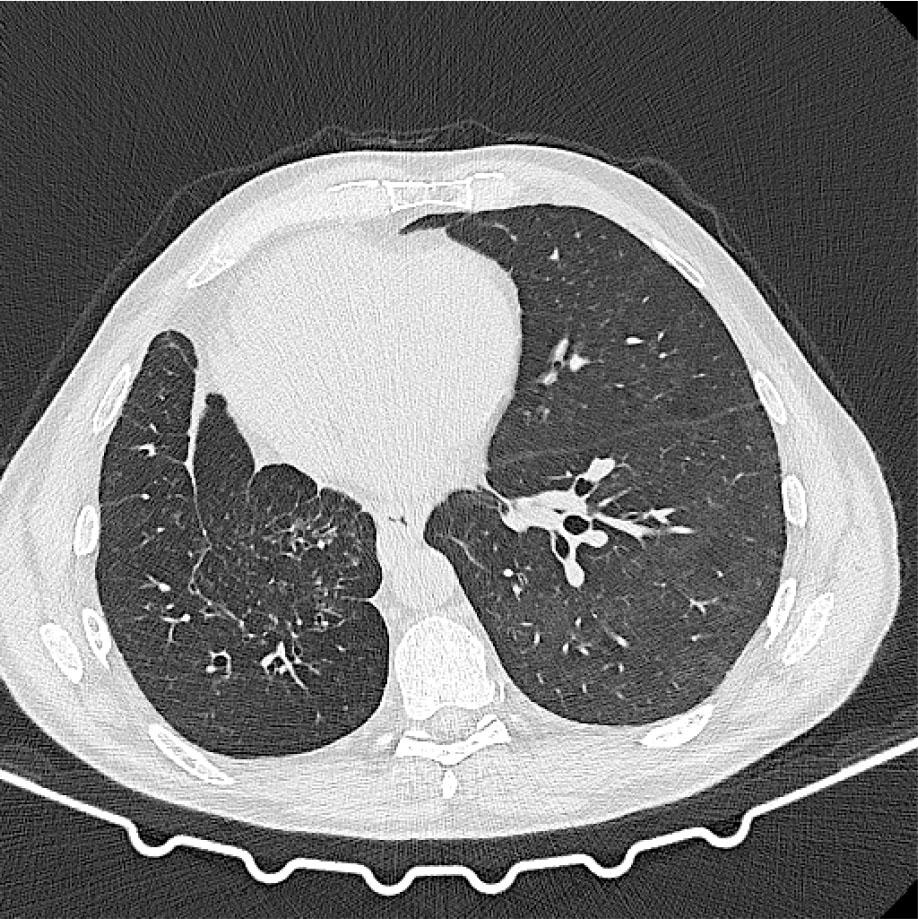

In September 2022, the patient complained of dyspnea on exertion and a dry cough for 2 weeks prior. A CT scan showed scattered ground-glass opacities in the left lung (figure 2). Amivantamab was suspended, and a bronchoalveolar lavage was performed, which showed alveolar lymphocytosis. The microbiologic examination identified Streptococcus pneumoniae, and antibiotic therapy was initiated. Imaging reassessment about 3 weeks later showed persistence of the lung opacities. A grade 2 CTCAE pneumonitis was assumed, and corticosteroid therapy with prednisolone 1 mg/kg was started. The patient reported improvement of symptoms, and a CT scan was performed after 5–6 weeks, which showed complete resolution of the radiologic abnormalities (figure 3).

CT scan after treatment with amivantamab showing scattered ground glass opacities in the left lung.